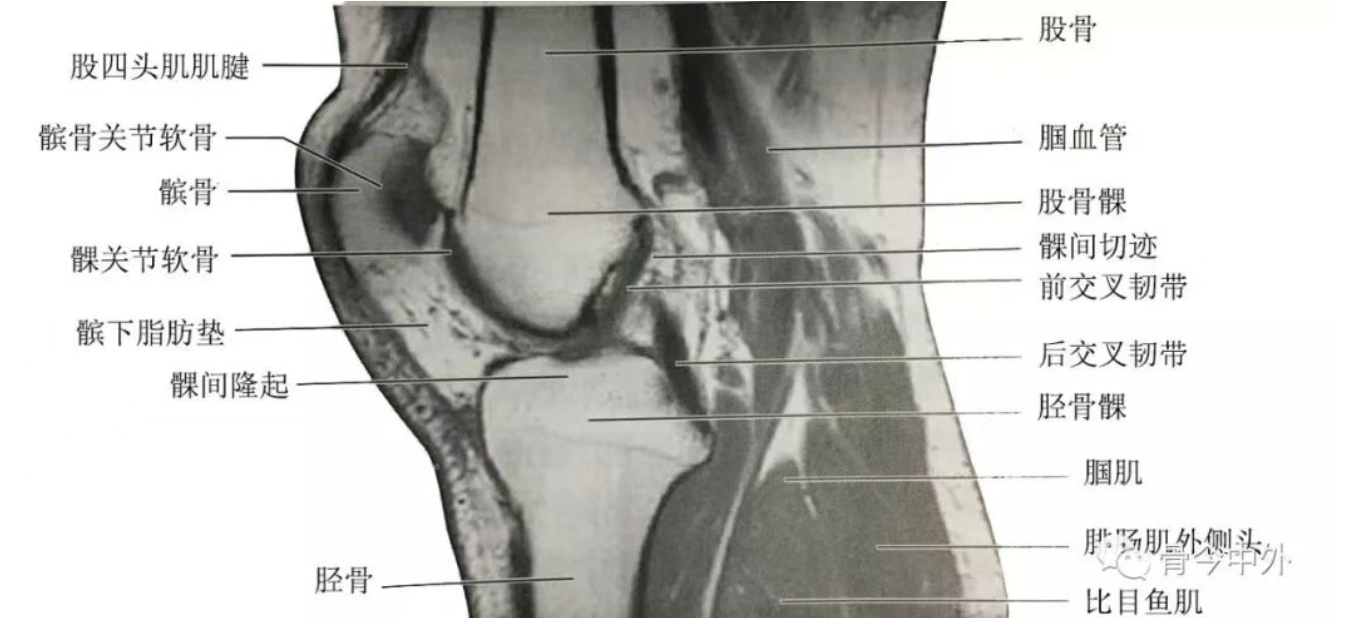

膝关节矢状断层

(1)膝内侧部矢状断层:该层面解剖关系结构如图

膝内侧部矢状断层

(2)膝正中矢状断层:该层面解剖关系结构如图

膝正中矢状断层